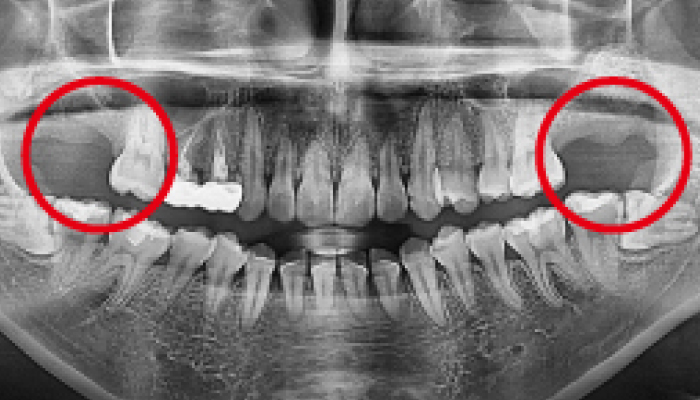

사랑니 발치 전후 사례

• 치료전

치료후